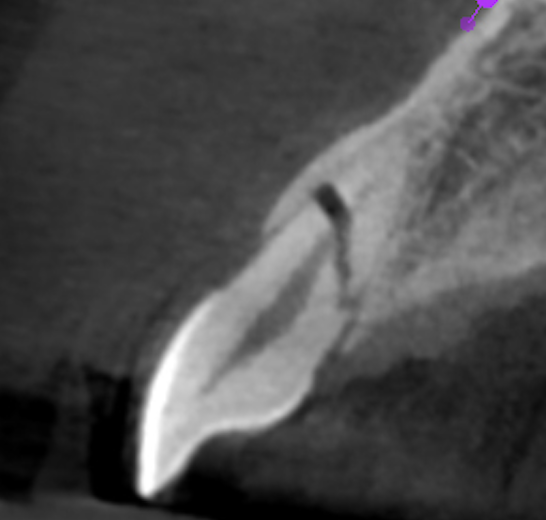

Apice Abierto

También ofrecemos tratamiento para los dientes permanentes jóvenes con desarrollo radicular incompleto. Esto puede ser un desafío para algunos odontólogos, pero contamos con la capacitación y experiencia necesarias para abordarlo eficazmente. Utilizamos técnicas especializadas y un seguimiento riguroso para asegurar la evolución del diente y minimizar riesgos.